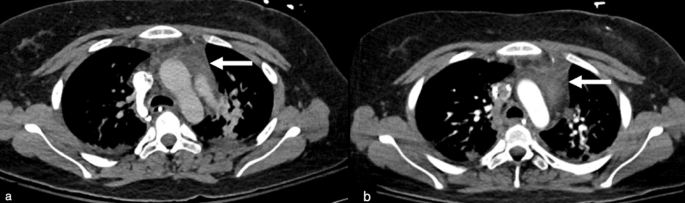

All chest CTs were reviewed by a pediatric radiologist with 8 years of experience (I.V.), who divided the patients into two groups according to the thymus size: Group 1 demonstrated a visual increase in thymus size after CAR T-cell therapy (Figs. 3 and 4). Group 2 demonstrated no change in thymus size or decreased size (i.e., no increase in thymus size) (Fig. 5). Then CT images were imported into OsiriX (Pixmeo, Bernex, Switzerland) and the thymus was outlined using the free-hand drawing tool. Automated 3D volume rendering was used to derive the volume (cm3) of the thymus (Fig s1). In addition, the same radiologist recorded the presence of lung, pleural, and mediastinal abnormalities. To complement this analysis, fluoroscopy images from interventional radiology (IR) procedures for peripherally inserted central catheter (PICC) line placement were reviewed when available. These IR fluoroscopic images, acquired at clinically relevant time points between the available chest CT and CAR T-cell infusion, provided additional reference for mediastinal silhouette and thymus size assessment. Specifically, the transverse thymic diameter was measured on these fluoroscopic chest images, allowing for comparison of thymic width before and after CAR T-cell therapy.

Axial chest computed tomography (CT) images of an 18-year-old female patient with ALL before and after CAR T-cell therapy. a) An axial chest CT image pre-CAR T-cell therapy shows the initial size and shape of the thymus. b) An axial chest CT image 32 days post-CAR T-cell therapy shows no significant change in the size and shape of the thymus.